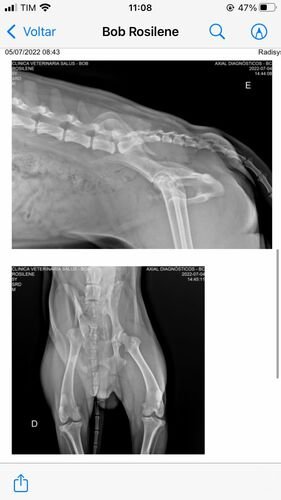

Bom, o Bob está com o quadril extremamente fraturado (conforme laudo disponível), inclusive o quadril dele está virado para o lado, ele precisa realizar um procedimento cirúrgico complexo e vai precisar utilizar placa (conforme foto do orçamento cirúrgico). Todos os custos de consulta e medicação eu consegui custear até agora (comprovantes disponíveis) mas infelizmente eu não consigo custear o valor da cirurgia em tão pouco tempo e peço ajuda de todos, todo valor é extremamente bem-vindo. Me ajudem a salvar a vida do Bob!

Laudo e Raio-x: